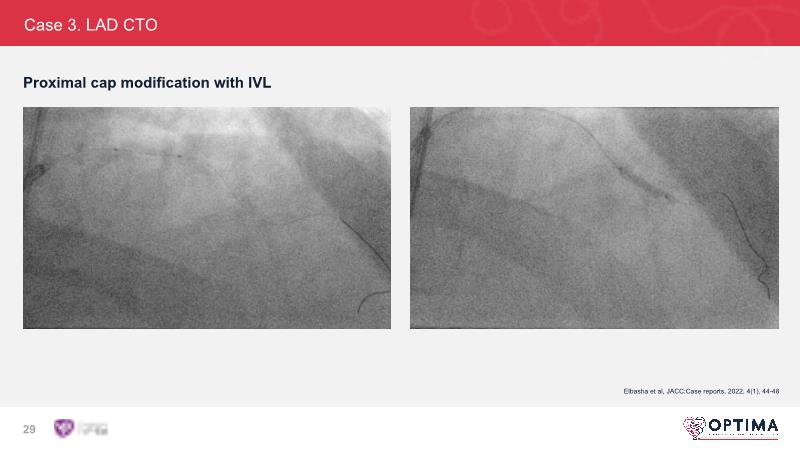

Cracking calcium: intravascular lithotripsy’s unique mode of action in treating calcified lesions – What's the evidence?

Watch this GulfPCR-GIM 2022 session to understand the unique mechanism of action of IVL, the use of intravascular imaging in calcium identification, the gender gap, disrupted CAD trials, and the evolution of treatment of calcified lesions together with the role of IVL.